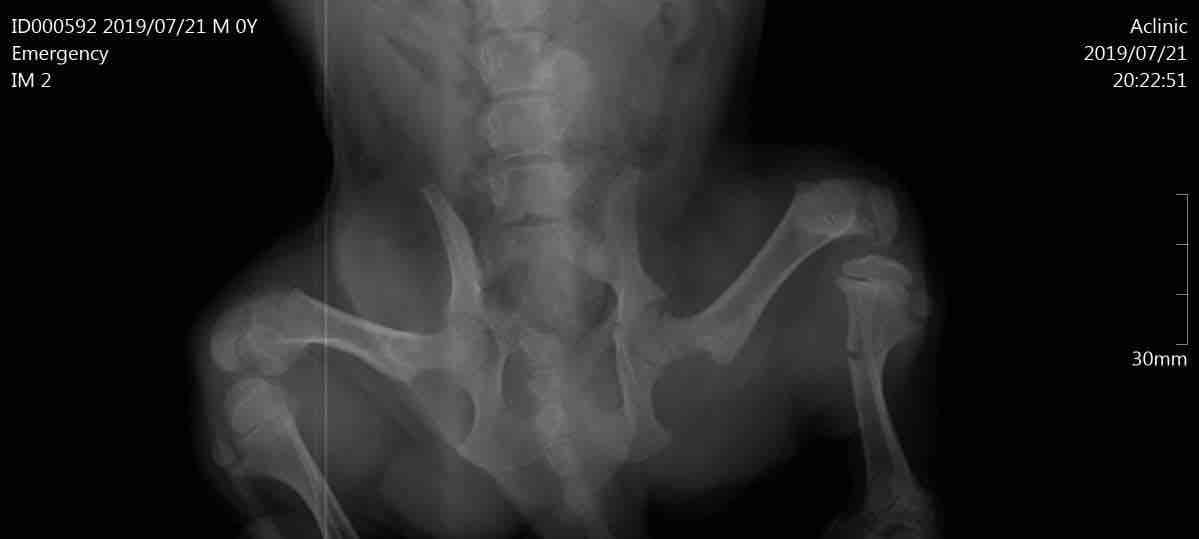

My dog put a supporting wrap on his leg 3 days ago but i cant make him stop move he wants to move in the home and when i put him in box and close it he start cry . That will lose him healing?! Or just slow his recovery? And have any solutions plz

This question includes photos that may contain sensitive content. Click to view.

With a broken bone, Biko should not be walking around at all. You need to keep him in a kennel to allow the leg the best chance to heal. He should also be in a splint, not a supportive wrap. He may need sedatives. I recommend to call the veterinarian and tell them what is happening. They can provide a splint as well as sedation for Biko. It will take 6 to 8 weeks for the bone to fully heal. I hope this helps and please feel free to post any additional questions.